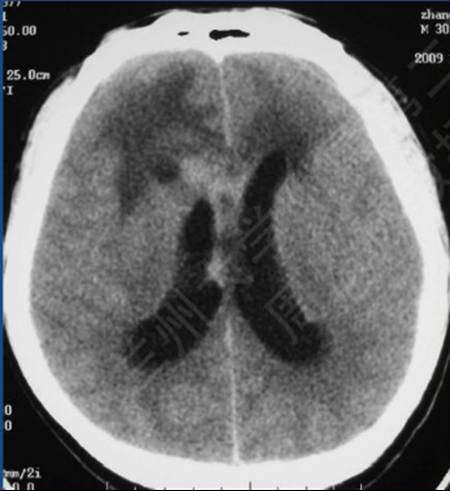

病例:男性,30岁,头痛2月

CT平扫

病理结果:富于淋巴浆细胞型脑膜瘤,WHO I级

2、CT密度较高,钙化少见。MR T1信号等或稍低、T2信号稍低或稍高,增强后呈明显强化;病灶内或边缘可见T1低信号、T2高信号区,增强后不强化;病灶边缘可见广泛增厚的脑膜强化。肿瘤界限模糊,似炎症,累及皮层,瘤周水肿明显(特征性表现)。

3、此亚型脑膜瘤有丰富的慢性炎细胞浸润,易伴发造血组织异常。病理上以上皮细胞增生伴大量淋巴细胞、浆细胞浸润为特点。